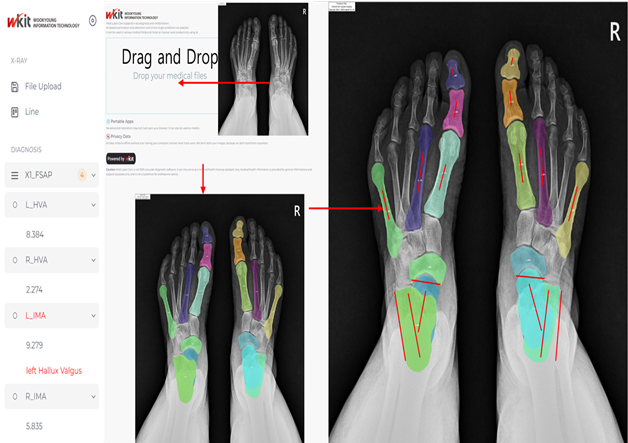

족부족관절 질환의 진단, 치료 모니터링을 위한 인공지능 학습용 멀티모달리티 DB 구축 – 영상자료 : 의료영상(X-Ray, Telegram), EOS, 보행분석, 보행동영상 – 영상 외 임상자료 : 인구학적 정보, 진단명, 수술명

– 족부족관절 질환의 진단, 치료 모니터링을 위한 인공지능 학습용 멀티모달리티 DB 구축 – 근골격게 DB를 AI Hub에 공개 후 총 6종 인공지능 모델 개발

| 라벨링 유형 | 키포인트(동영상/이미지), 세그멘테이션(이미지) | 라벨링 형식 | JSON |